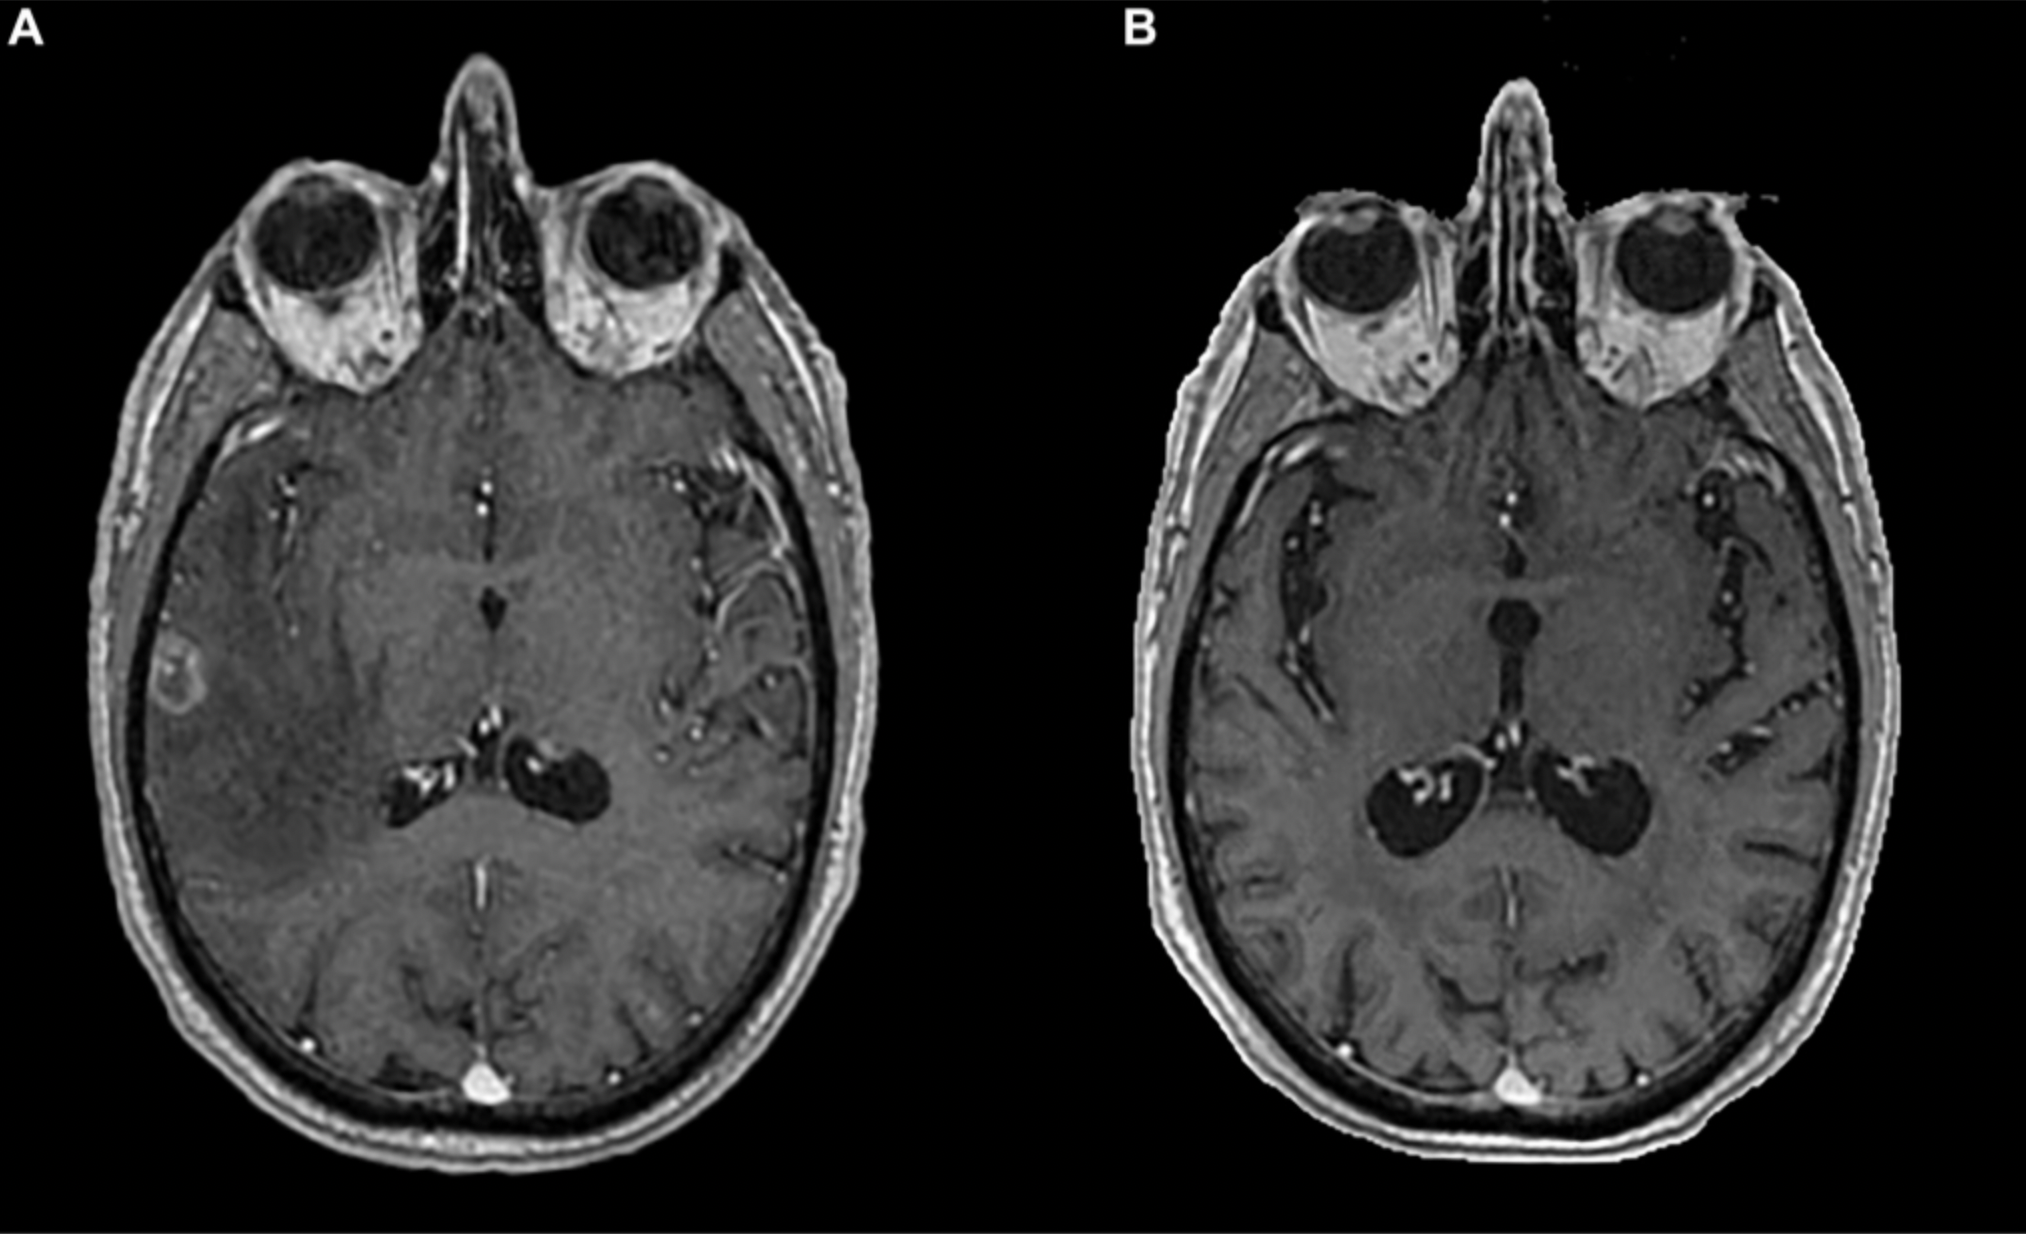

Long-lasting Immunotherapy Response in Stage IV Lung Cancer with Brain Metastasis

October 18, 2024